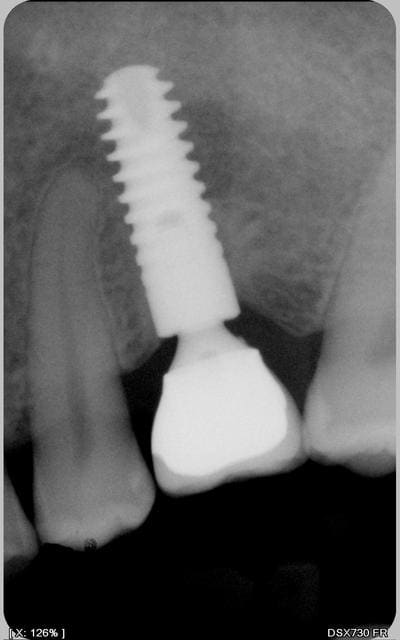

je vais vous envoyer la dernière rvg de ce fut et vous verrez la surprise ... dr fouilla a fait repousser l'os ou yen avait plus et toc !

en fait à l'époque je n'avais surtout pas cureté le fut mais au départ fait quelques instillations et pis j'avais à deux reprises mis un mélange d'AB en local en sringues automélangeuses et je ne me souviens plus du tout du nom du produit (je pourrai en insistant bien le retrouver mais m'ne fout aujourd'hui)et wait and see . promis la photo bientôt

pour répondre à la question précédente je pense que la densité osseuse (typeI+++)n'est pas étrangère au problème dans ce cas précis si tu pense à l'absence de microfiletage du col depuis la macrogéométrie du fût a changé et ça aussi n'est pas étranger au problème et que dire du blocage du forêt...